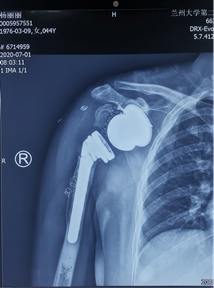

韵向东主任考虑到患者年龄较轻,生活质量要求较高,为了最大限度地恢复保留患者的肩关节功能,决定结合与国际接轨的3D打印数字化假体最新技术,个性化定制了反肩关节假体,降低了因关节畸形及缺损,周围肩袖缺失等增加的手术难度及风险,同时也大大缩短了手术的时间,让反肩置换更加精准,患者满意度大幅度提高!

术前个性化定制3D打印-反肩关节置换假体,结合病情设计修补重建及定位点